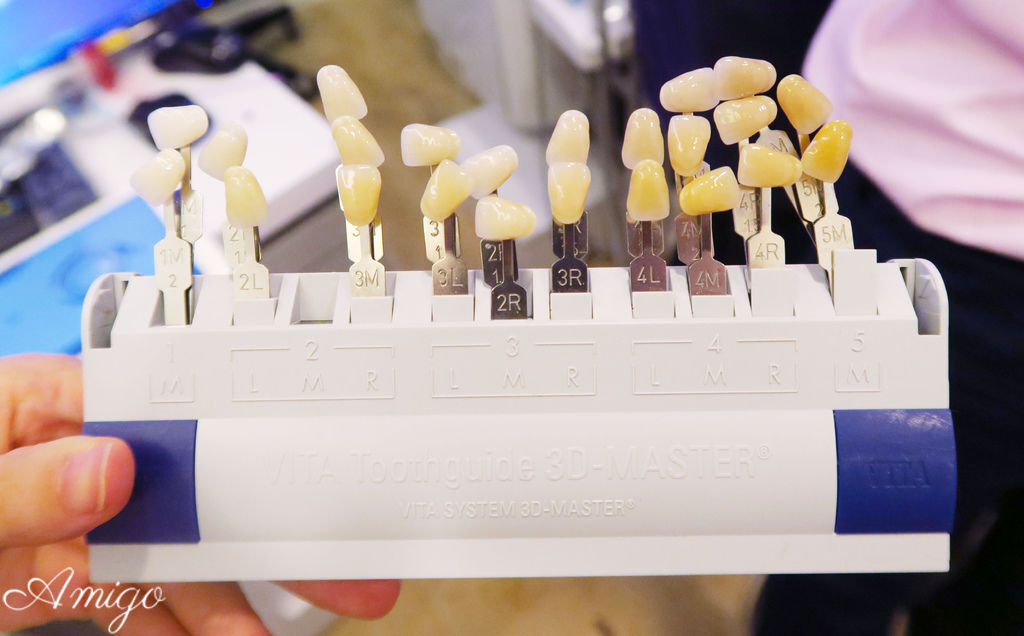

技師透過德國VITA比色儀 來比對前面一顆牙齒的顏色

機器上立刻顯示出與牙齒接近的瓷塊色號

再以牙齒的比色板 放在牙齒旁邊做實際上的顏色確認

與醫師討論出確定出要做的全瓷冠牙套

牙齒比色板 ▼▼▼

德國VITA比色儀▼▼▼